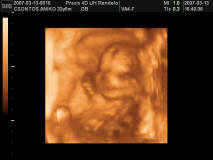

ANikó: nekünk nincs uh képünk! Ahogy észrevettem a Dél-Pestiben egy normális Wc sincs, nemhogy uh kép! De majd a 24. hét körül elmegyünk 3D-s uh-ra, akkor már szerintem biztos lesz a neme! Ha kisfiú, csak nem lesz szégyenlős.